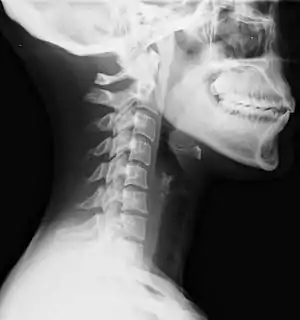

Lateral view X-ray of whiplash showing a loss of normal lordosis of the cervical spine | |

Diagnosis occurs through a patient history, head and neck examination, X-rays to rule out bone fractures and may involve the use of medical imaging to determine if there are other injuries.[26]